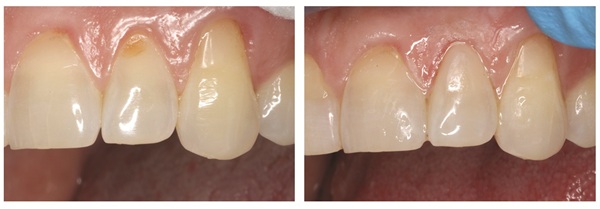

Fig. 2: Before and after on tooth #12 DO using GrandioSO 4U shade A1 cluster

As seen in Figure 1, we were able to seamlessly cover the dark yellow circle of dentin seen in the before photo while blending the composite covering the gingival two-thirds of the enamel to rebuild what was lost from erosion. Our patient was so thrilled with the outcome, that after we completed the required work on #10 and #12 (Fig. 2), she asked if she could have her other four Class V restorations on #7–9 completed at her next visit. With one small filling we gained big trust with a patient that began her visit with fear and anxiety and created a lasting, positive impression. Note that this was done fast with only one shade, yet you can see a gradation of shade blending over the entire tooth. Once cured we simply shaped and polished and she was asking for more.